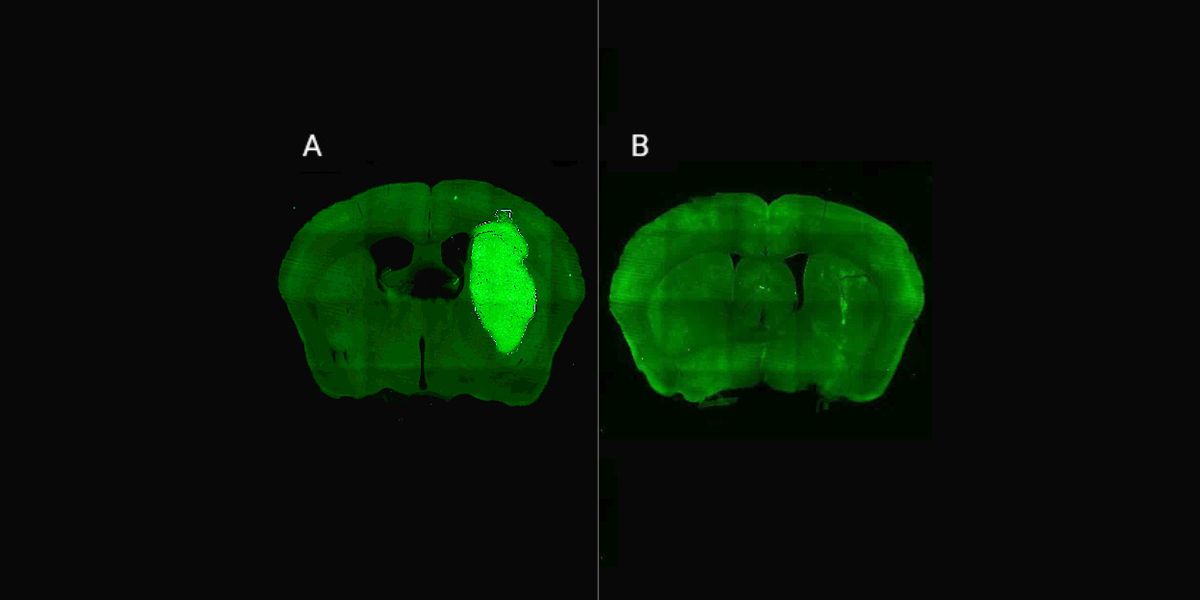

En estudios in vivo, el equipo liderado por Candolfi utilizó ratones inoculados en el cerebro con neuroesferas que contienen lesiones características de los tumores humanos que fueron desarrollados por el laboratorio de la científica argentina y colaboradora del estudio María Castro en la Universidad de Michigan, en Estados Unidos. Para tratar los tumores in vivo, los equipos de Candolfi y de la también científica del CONICET Flavia Zanetti, del Instituto de Ciencia y Tecnología César Milstein (CONICET- Fundación Pablo Cassará), desarrollaron un vector adenoviral que expresa la molécula o péptido P60 al interior de las células tumorales.

“Esta estrategia permite la expresión sostenida de P60 en la zona del tumor, facilitando la terapia y reduciendo la probabilidad de efectos colaterales sistémicos. Una inyección intratumoral del vector inhibió el crecimiento del tumor y mejoró notablemente la respuesta a la quimioterapia, llevando a la erradicación del tumor y sobrevida a largo plazo en un tercio de los ratones con tratamiento combinado”, afirma Candolfi. Y agrega: “No observamos efectos neurotóxicos con ninguno de los tratamientos empleados, por lo tanto, esta estrategia tendría buen perfil de seguridad para tratar estos tumores”.